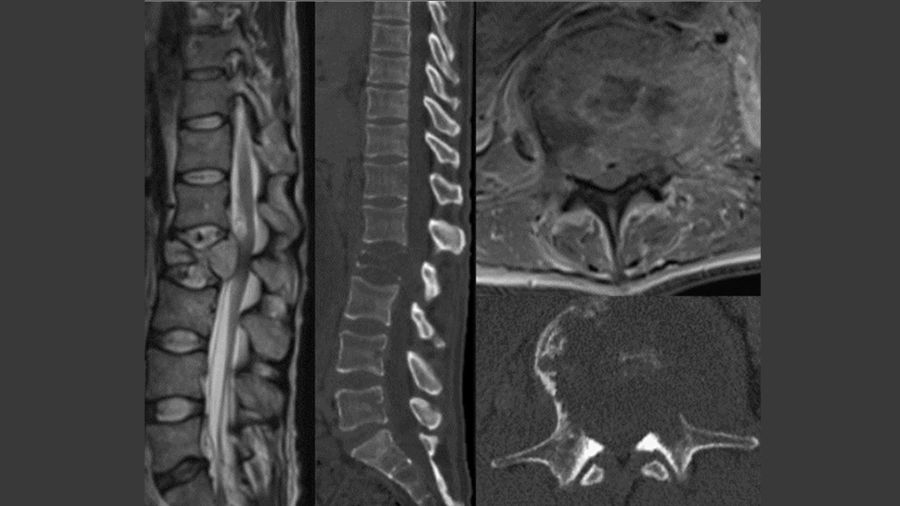

Case 2: A 71-year-old man presents with one week of back pain.

He was diagnosed 5 months ago with NSLC adeno-carcinoma also with an EGFR mutation and started on osimertinib. He has progressed through targeted therapy and recently started chemotherapy.

One month ago, he was found to have metastases to the liver and pelvis and was started on pembrolizumab/ carboplatin/ pemetrexed. He is now found to have an L2 pathologic fracture with retropulsion. He is ambulatory and full strength. His ECOG performance status is 2 and his SINS is 15. The patient seems to have progressed through targeted therapy but just started chemotherapy recently, which still leaves room for further systemic options.

Patient is offered separation surgery plus stabilization.